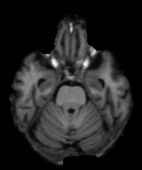

We evaluate on several datasets, where we can compare to earlier registration approaches. We use the network with inverse-consistent SVF networks backed by U-Nets and inverse-consistent affine networks backed by ConvNets222Specifically, networks.tallUNet2 and networks.ConvolutionalMatrixNet from the library icon_registration version 1.1.1 on pypi. We rely on local normalized cross-correlation as our similarity measure, with , and regularize the SVF networks by the sum of the bending energies of their velocity fields, with . We train end to end, minimizing for 100,000 iterations ( days on 4 NVIDIA A6000s) with Adam optimization and a learning rate of -. In all cases, we normalize images to the range (0, 1). We evaluate registration accuracy with and without instance optimization [26, 23]. Without instance optimization, registration takes 0.23 seconds on an NVIDIA RTX A6000 on the HCP [24] dataset. With instance optimization, registration takes 43 seconds.

HCP Brain MRI We train on 1076 brain-extracted T1w images from the HCP dataset [24] and test on a sample of 100 pairs between 36 images via mean Dice over 28 midbrain structures [20, 21]. We train and execute the network at [130155130], then compute the Dice score at full resolution.

OASIS Brain MRI We use the OASIS-1 [12] data preprocessed by [9]. This dataset contains images of 414 subjects. Following the data split in [14], we train on 255 images and test on 153 images555Due to changes in the OASIS-1 data, our test set slightly differs from [14]. We evaluate all methods using our testing protocol so that results are consistent.The images in the dataset are of size [160192224], and we crop the center of the image according to the preprocessing in [14], leading to a size of [160144192]. During training, we sample image pairs randomly from the train set. For evaluation, we randomly pick 5 cases as the fixed images and register all the remaining 148 cases to the 5 cases, resulting in 740 image pairs overall.

| Moving Image | Warped Image | Fixed Image | Moving Image | Warped Image | Fixed Image |